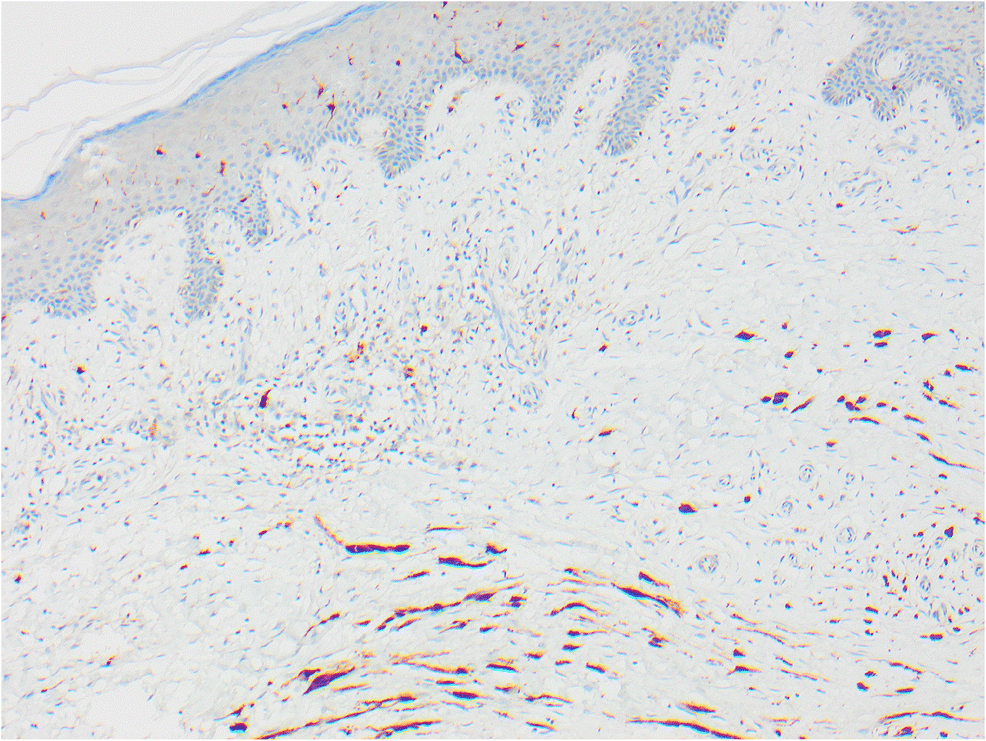

Fig. 3

The skin seen in Fig. 2 shows elongated spindle cells positive with S100

In 2015, 10 years after excision of the primary SSM on the calf, three subcutaneous nodules were identified near the original scar. On excision, these were shown to be recurrent melanoma with an epithelioid component similar to the original, but merging with a spindle cell desmoplastic component. The deeper spindle desmoplastic component was S100-positive but HMB45-negative, in contrast to the original melanoma which was HMB45-positive.